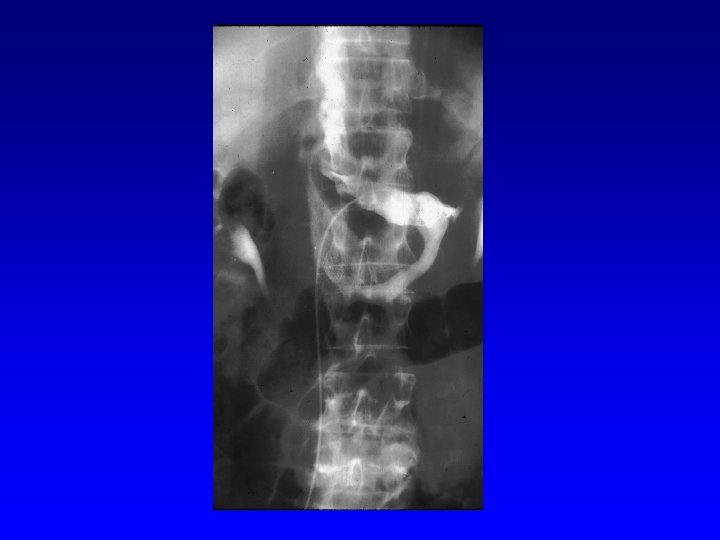

IVC Filter Removal Straight forward and Complex

Removal of an “Intravascular Foreign Body” Straight forward Loop snare Grasping device Complex Multiple devices used including angioplasty balloons, bronchoscopy forceps, and the“in situ” snare technique.

Retrieval with a snare and a long sheath or guiding catheter Günther Tulip (Cook) Celect (Cook) Opt Ease (Cordis Endovascular) Option (Angiotech) G 2 X, Eclipse, Meridian (Bard)